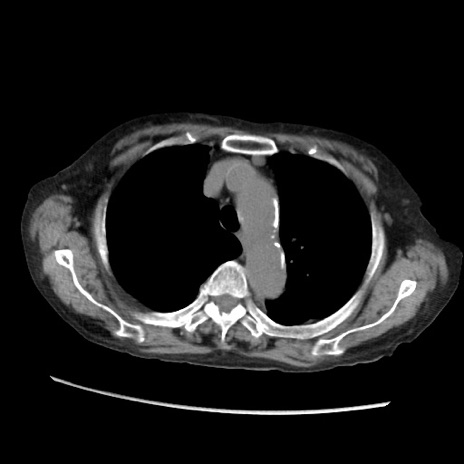

症例31(横断像)

【症例】80歳代 女性

【主訴】腹部膨満感

【現病歴】他院にて肝硬変にてフォロー中。1週間前から便秘、腹部膨満感、臍部腫瘤あり受診となる。

【既往歴】肝硬変

【身体所見】腹部膨隆あり、皮膚変化なし、疼痛なし。

【データ】WBC 4600、CRP 0.25